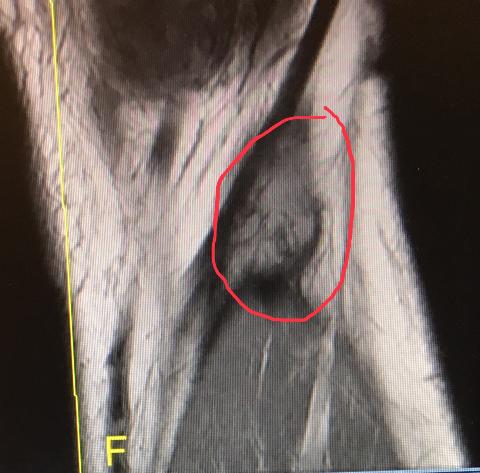

I had a set of issues with the left knee in 2005/2006 -Torn miniscus, Excised tumor, Synovectomy, aggressive radiation. Radiation accelerated the degradation of that knee to the point it was gunnysack by spring 2018 with some growths reappearing.